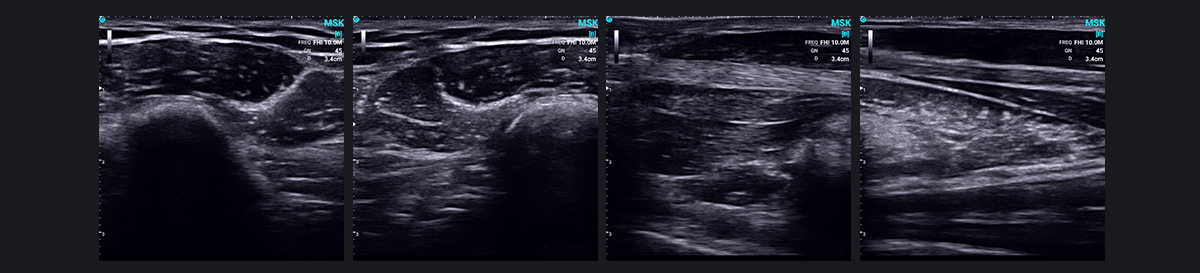

¼¡Èâ¹Ç÷À³¬Éù£¨MSK£©½üÄêÀ´ÒѳÉΪһÏîÍ»ÆÆÐÔ¼¼Êõ£¬ÀûÓÃ¸ßÆµ³¬ÉùÀ´Õï¶Ï¼¡Èâ¹Ç÷Àϵͳ¼²²¡¡£ËüÌṩ¼¡Èâ¡¢¼¡ëì¡¢ÈÍ´ø¡¢ÖÜΧÉñ¾ºÍÆäËûdz±íÈí×éÖ¯½á¹¹µÄÇåÎúͼÏñ£¬Ê¶±ðÑ×Ö¢¡¢Ö×Áö¡¢ËðÉ˺ͻûÐεÈ×´¿ö¡£

MSK ³¬Éù²¨ÔÚÕï¶Ï¹Ø½Ú¼²²¡·½ÃæÌرðÓÐЧ£¬°üÀ¨Àà·çʪÐԹؽÚÑ׺ÍÍ´·çÐԹؽÚÑס£Ëü»¹ÓÐÖúÓÚ¼ì²â´úлºÍÈ«Éí¼²²¡ÒÔ¼°Ïà¹ØµÄ¹Ø½Ú²¡£¬Ìṩ¸÷ÖÖ²¡Ö¢µÄÈ«ÃæÊÓͼ¡£

´ËÍ⣬³¬Éù²¨µÄʵʱ¶¯Ì¬³ÉÏñ¹¦ÄÜ¿ÉÒÔ¼ì²âºÍ¹Û²ì½öÔÚÔ˶¯ÆÚ¼ä»òÌØ¶¨Î»ÖóöÏÖµÄÒì³£»ò²¡±ä£¬ÀýÈ缡ëìºÍÉñ¾ÍÑλ»ò¼ç²¿×²»÷×ÛºÏÖ¢¡£Ëü»¹¿ÉÒÔͬʱɨÃèÊÜÓ°ÏìµÄÒ»²àºÍ½¡¿µµÄÒ»²à£¬´Ó¶øÓÐÖúÓÚ¶¯Ì¬±È½Ï×éÖ¯½á¹¹ÒÔʶ±ðÒì³£Çé¿ö¡£